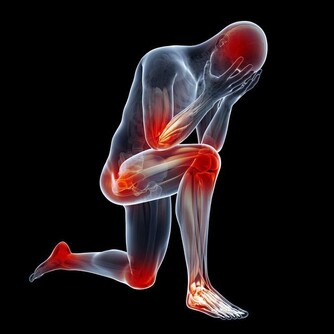

亞健康人群,往往以疲勞、睡眠紊亂、疼痛等症狀表現為主,常伴有記憶力下降、注意力不集中、思維緩慢、反應遲鈍等情況。

我們也可以進行慢跑、太極、八段錦、瑜伽等舒緩的運動項目,可以疏通人體的經絡,長期堅持就能促進體內氣血的運行狀況,提升身體免疫力。